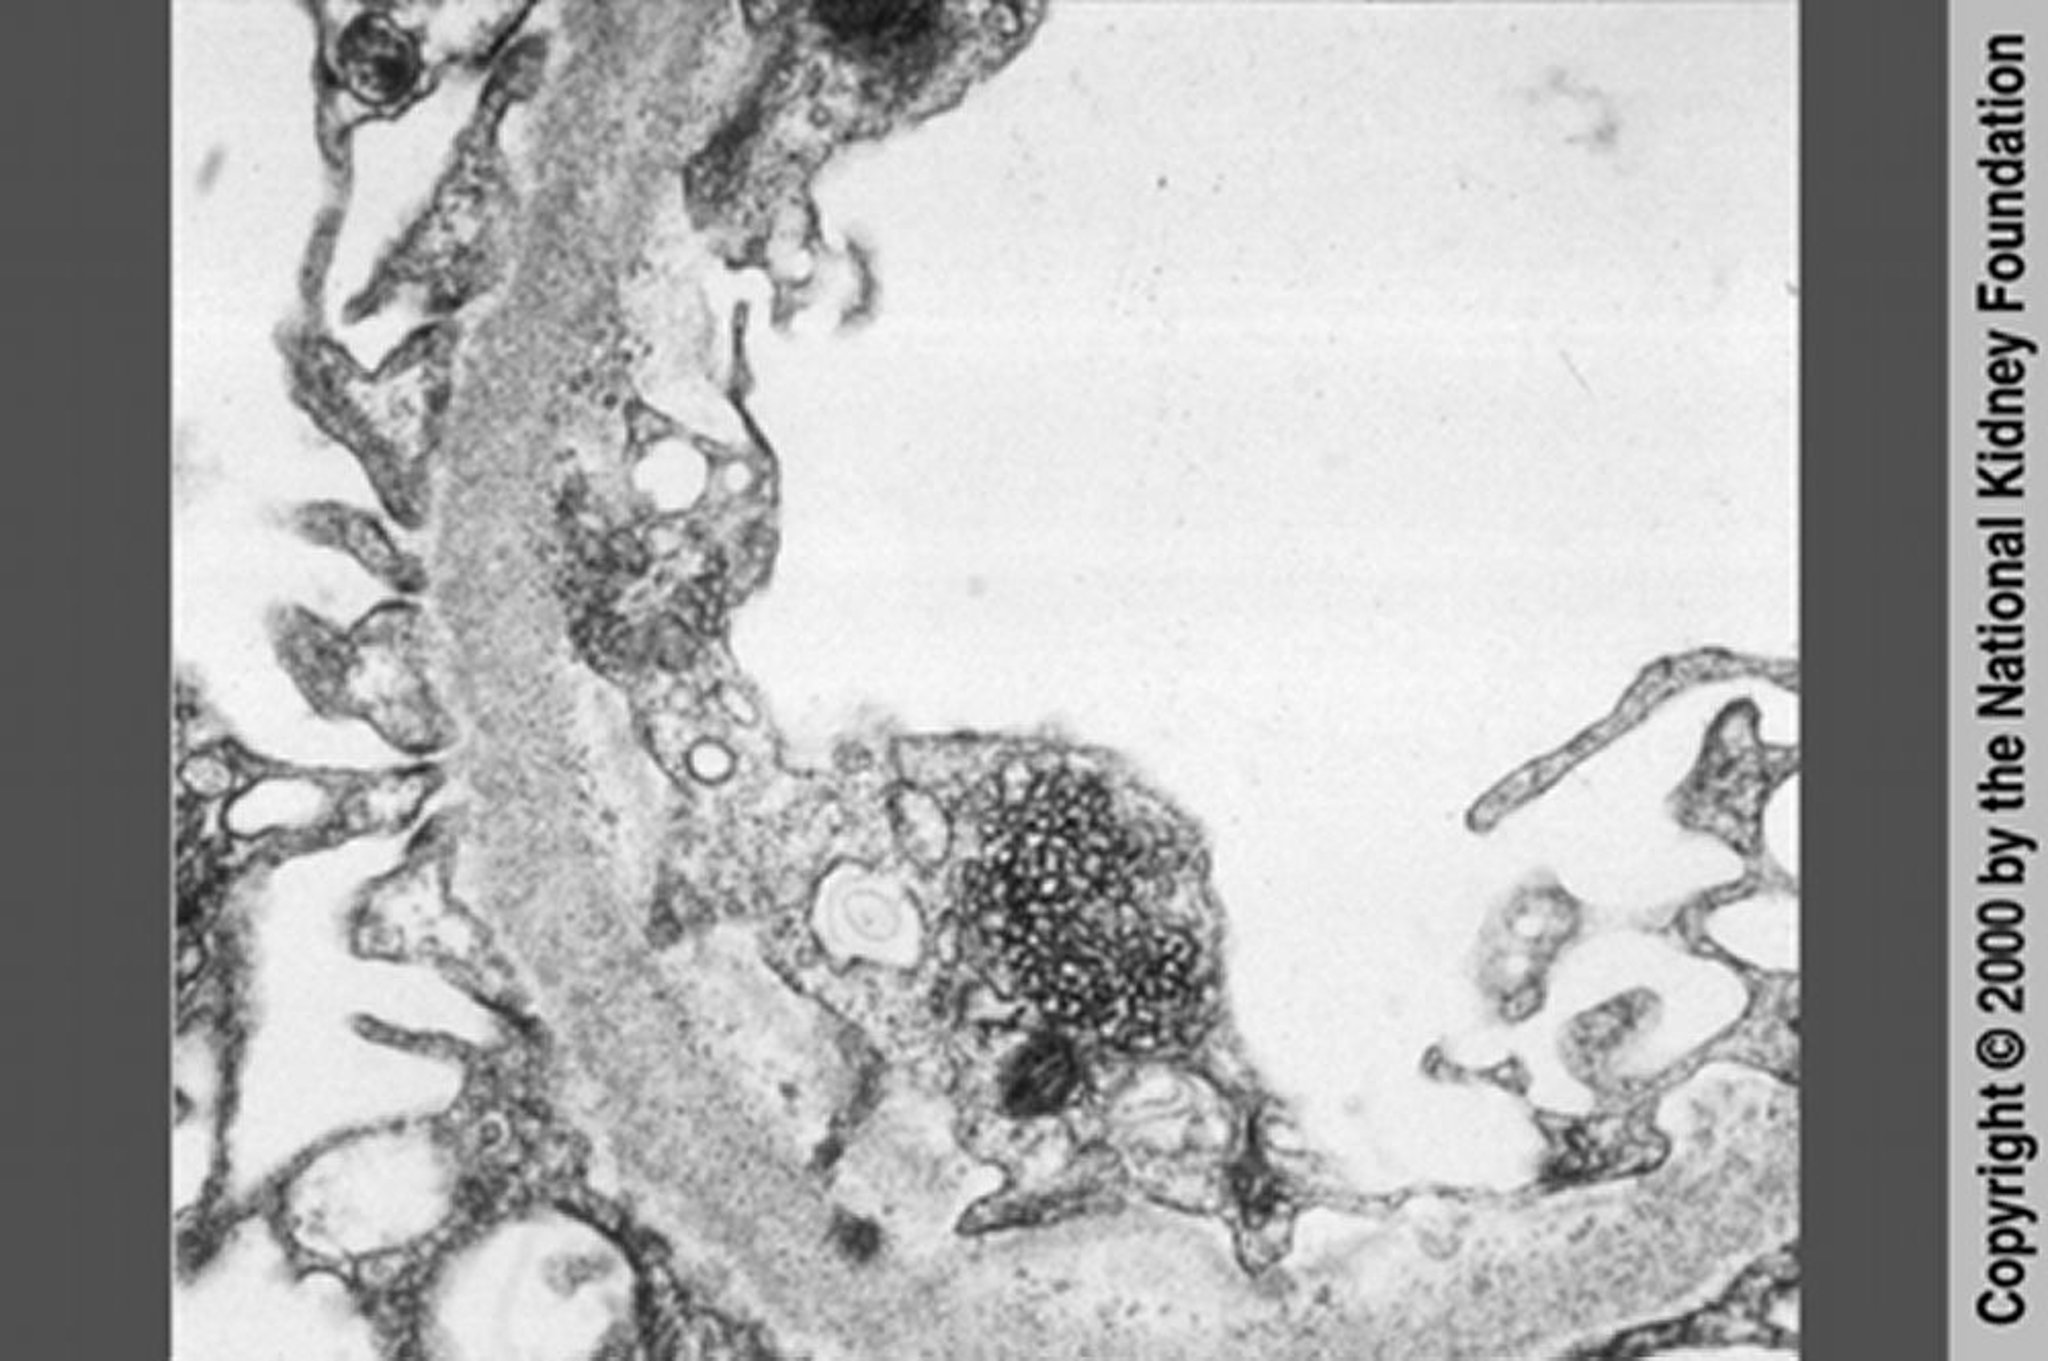

HIV-assoziierte Nephropathie (retikuläre Einschlüsse)

Eine HIV-assoziierte Nephropathie kann durch retikuläre Einschlüsse im Zytoplasma von Endothelzellen in der Transmissionselektronenmikroskopie von fokal-segmentaler Glomerulosklerose unterschieden werden (×20.000). Diese retikulären Einschlüsse sind jedoch dank der hochaktiven antiretroviralen Therapie selten geworden.

Image provided by Agnes Fogo, MD, and the American Journal of Kidney Diseases' Atlas of Renal Pathology (see www.ajkd.org).